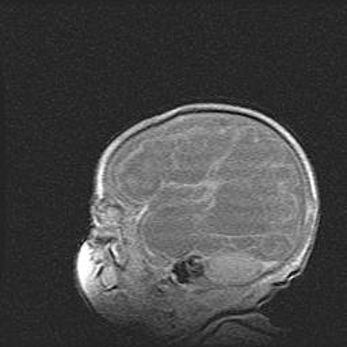

Множественные кисты обоих полушарий головного мозга, наибольшая из них в правой затылочной области. Ассиметричная атрофическая гидроцефалия.

Возраст: 7 месяцев

Вес: 5660 г

Пол: мужской

Окружность головы: 41,5 см

Срок гестации: 28-29 недель

Кисты головного мозга развиваются в результате многоочаговых некрозов вещества мозга и возникают вследствие перенесенной перинатальной инфекции, менингитов, энцефалитов, асфиксии, родовой травмы, расстройств мозгового кровообращения различного генеза. Образованию кист в веществе головного мозга плодов и новорожденных способствуют такие факторы, как высокое содержание в нем воды, недостаточная (или отсутствие) миелинизация и слабая астроглиальная реакция на повреждение.

Кисты могут сочетаться с гидроцефалией и другими поражениями головного мозга.